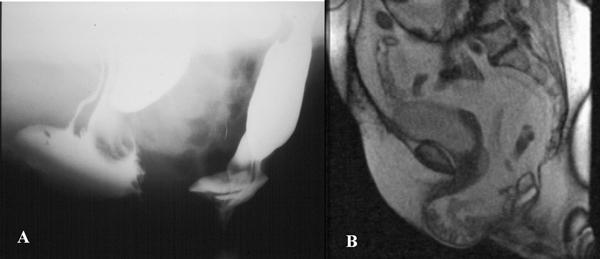

The prevalence of pelvic floor hernias at conventional radiology was higher if compared with that at MRI. Concerning the hernia content, there were significantly more enteroceles and sigmoidoceles on conventional radiology than on MRI, whereas, in relation to the hernia development modalities, the prevalence of elytroceles, edroceles, and Douglas' hernias at conventional radiology was significantly higher than that at MRI.

与MRI相比,传统放射学检查中盆底疝的患病率更高。关于疝内容物,传统放射学检查中肠膨出和乙状结肠膨出明显多于MRI检查;而关于疝的发展方式,传统放射学检查中阴道膨出、会阴疝和Douglas疝的患病率明显高于MRI检查。